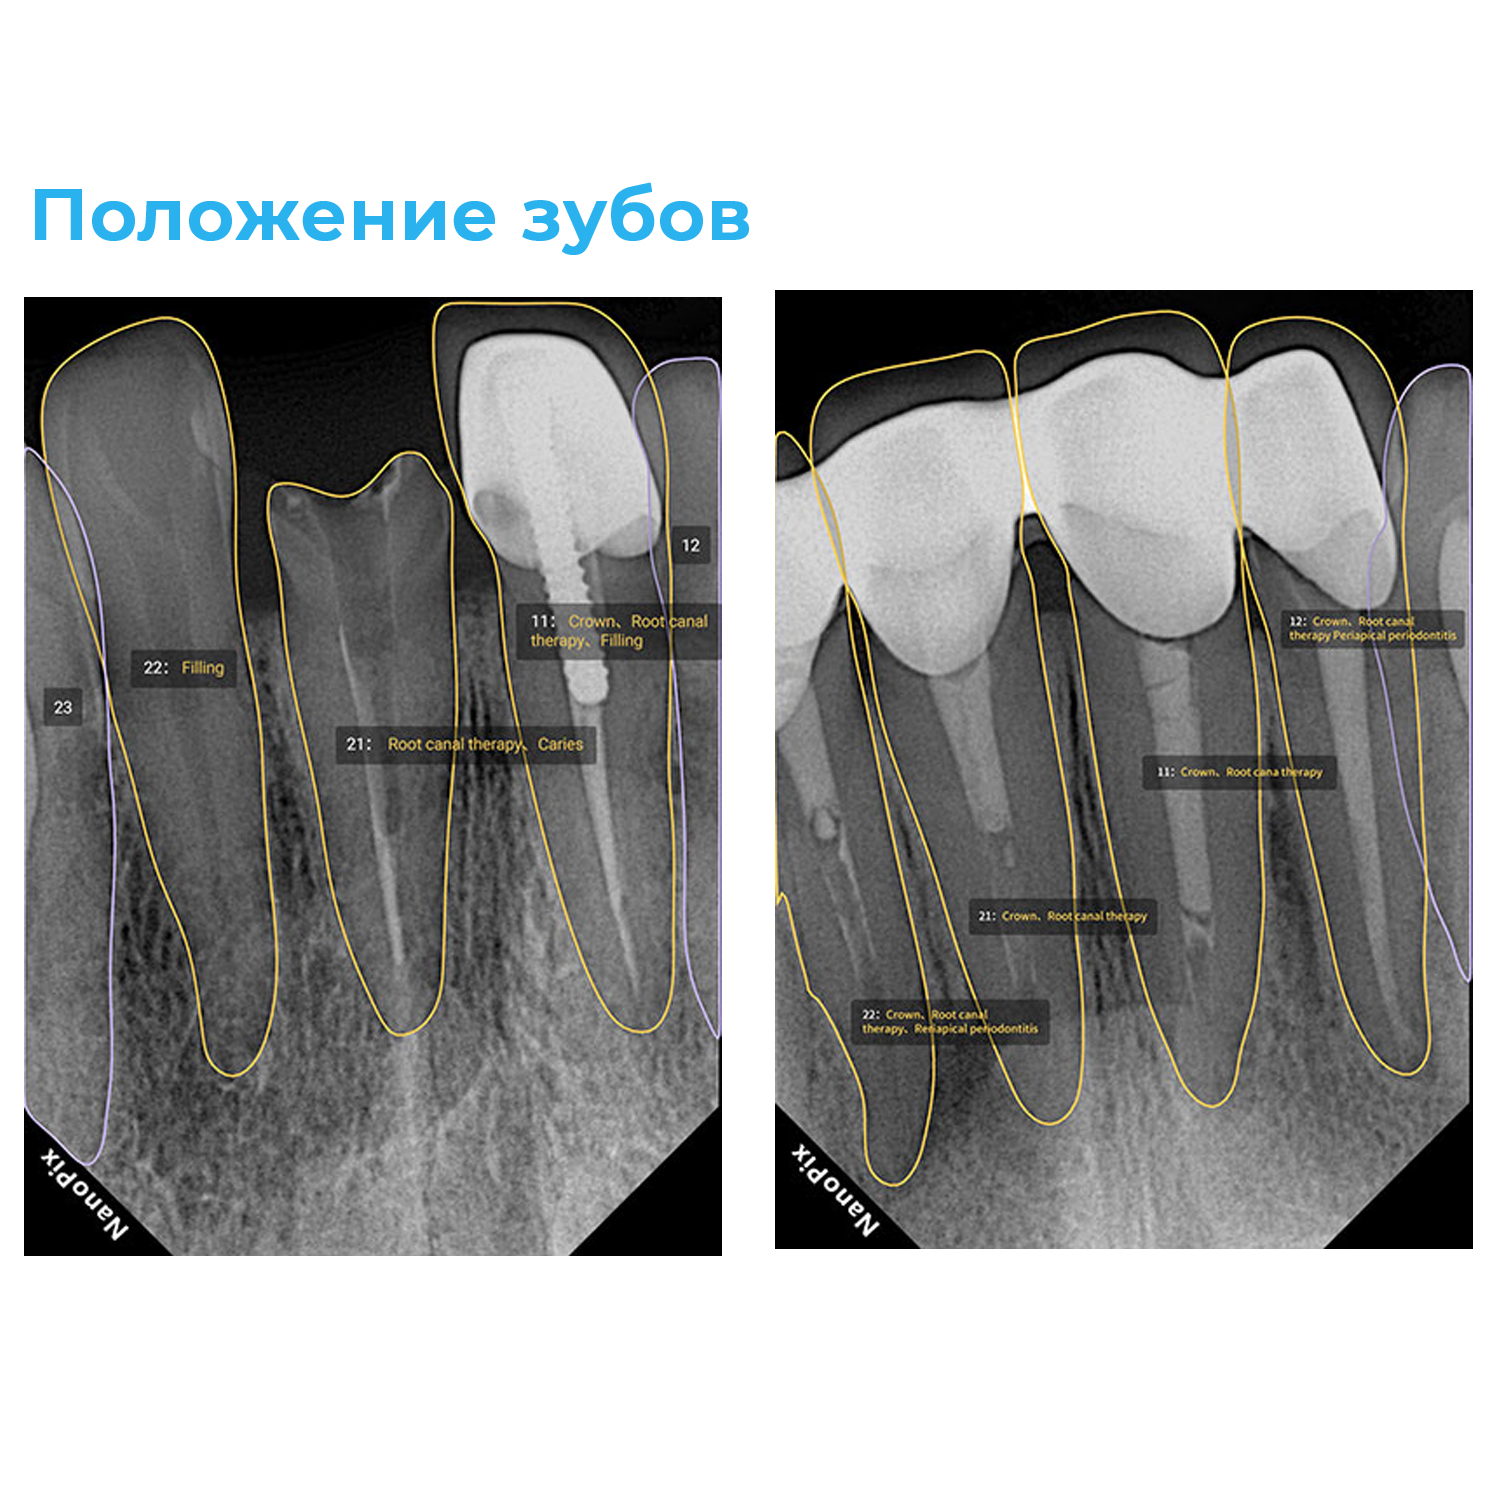

Прибор оснащён высокочувствительным сенсором, с помощью которого устройство фиксирует и передаёт изображение в цифровом виде на компьютер. Принцип работы заключается в следующем: цифровой радиовизиограф размещается в ротовой полости пациента за зубами. С щёчной стороны дентальный рентгеновский аппарат выпускает в направлении радиовизиографа рентгеновские лучи. Лучи, проходя через ткани зуба, фиксируются на радиовизиографе, и полученная информация отображается на экране компьютера. Уникальная технология искусственного интеллекта Nano AI распознаёт зубные патологии, выделяя их цветом и предлагая возможные способы лечения.